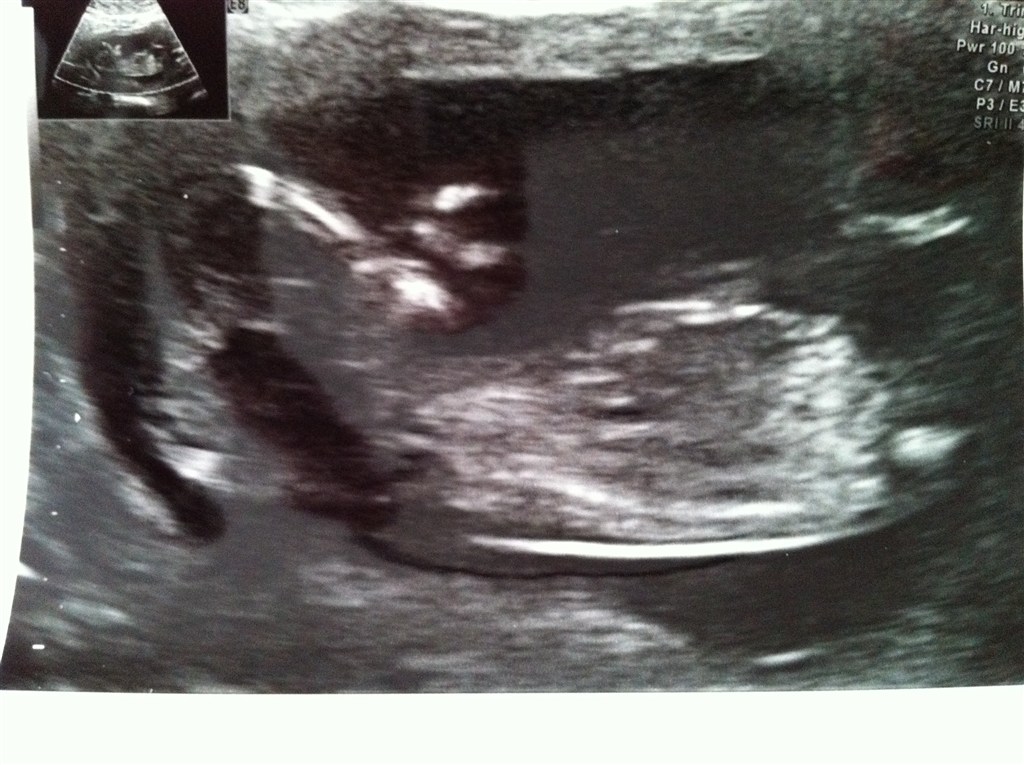

Billedspam af Nakkefoldsscanning i dag den 11.06.2012.

Har været til nakkefoldsscanning i dag og det var godt nok ubeskrivelig den oplevelse, kunne ligge der i flere timer, hvis jeg fik lov hehe. Vores guldklump er alledere 10 cm

Vedhæftede fotos (klik for at se i fuld størrelse)